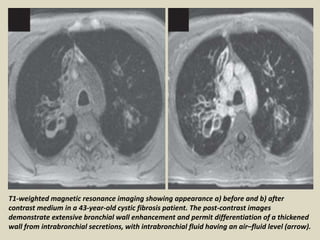

T1-weighted magnetic resonance imaging showing appearance a) before and b) after

contrast medium in a 43-year-old cystic fibrosis patient. The post-contrast images

demonstrate extensive bronchial wall enhancement and permit differentiation of a thickened

wall from intrabronchial secretions, with intrabronchial fluid having an air–fluid level (arrow).